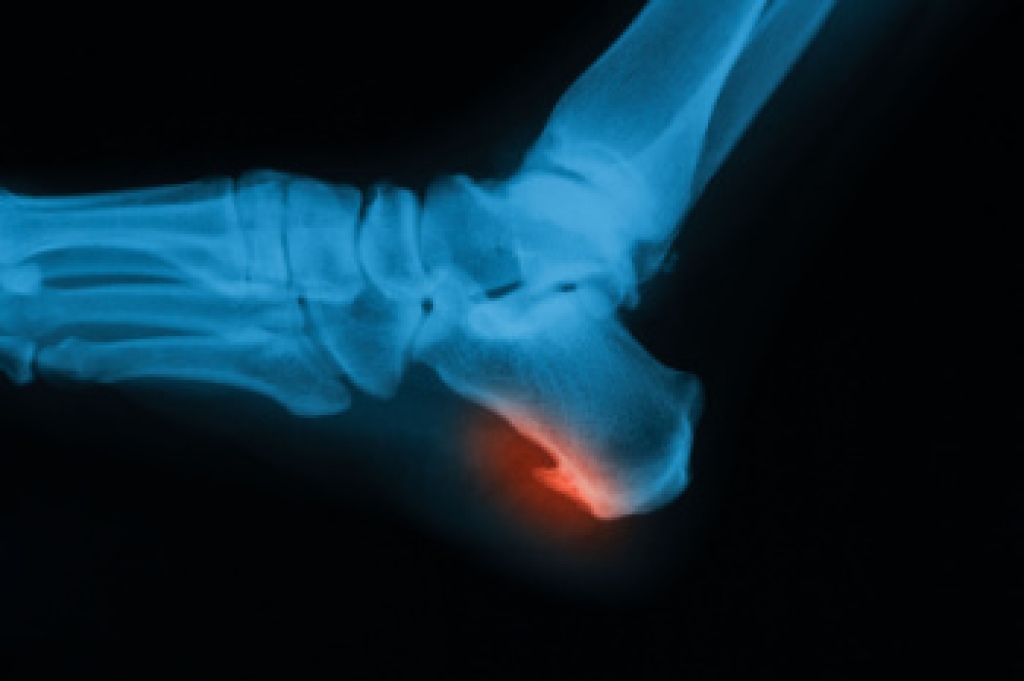

A heel spur is a bony growth that often develops on the underside of the heel bone due to calcium deposits forming over time. It often occurs as a result of repeated strain on foot muscles and ligaments. Causes include aging, joint stress, and being overweight. Poorly fitting footwear and participating in high impact athletic activity also may contribute. Risk factors involve prolonged standing, flat feet or high arches, and improper support during movement. Symptoms include sharp heel pain, especially with the first steps after rest, and ongoing discomfort while walking. A podiatrist can diagnose heel spurs through an examination and imaging. Treatment options include custom orthotics, stretching exercises, and supportive footwear. If you have heel pain, it is suggested that you consult a podiatrist who can accurately diagnose and treat heel spurs.

Heel spurs are formed by calcium deposits on the back of the foot where the heel is. This can also be caused by small fragments of bone breaking off one section of the foot, attaching onto the back of the foot. Heel spurs can also be bone growth on the back of the foot and may grow in the direction of the arch of the foot.